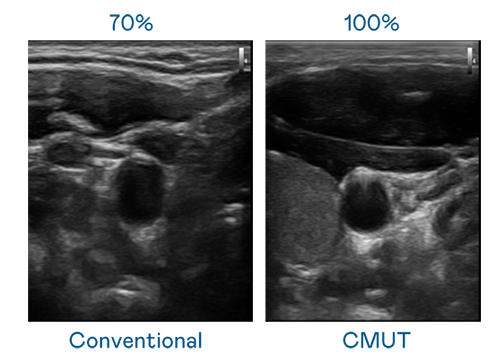

CMUT 技術是一種用電容式微機電元件來產生超音波訊號的技術。與傳統 PZT 壓電式技術相比,CMUT 頻寬增加 30%,更寬頻的超音波訊號讓影像解析度大幅提升,是實現高影像品質醫療超音波掃描、促進精準醫療發展的關鍵技術。

大頻寬帶來超清晰影像

超音波影像的解析度高低,首先取決於探頭能發出的訊號頻寬。彩神Vll官网 CMUT 可提供高清晰的超音波訊號,提供高頻寬、高靈敏度、影像紋理細節更高的超音波影像,協助醫護人員縮短影像判讀時間及利用精準的醫療影像進行診斷。